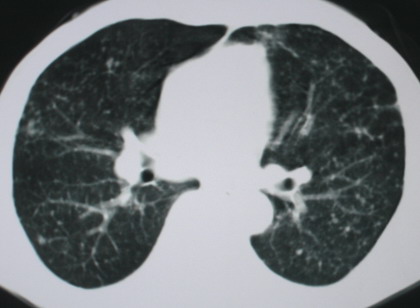

以下是引用卜一在2008-6-3 19:33:00的发言:[br]双肺结节,以双上肺分布为多,期间搀杂片状致密影及索条致密影。考虑:继发性肺结核伴血型播散可能性大。不除外肺泡ca的可能!另:椎体退变!

以下是引用panyishengct在2008-6-3 21:09:00的发言:[br]双上肺弥漫性小结节影,纵隔窗内钙化淋巴结影,考虑矽肺或/和tb可能性较大,不除外肺ca可能。腰椎考虑退变。 [br][br]